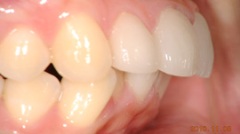

審美的治療の実例

出っ 歯が気になって来院した患者様です。海外に行くことが決まっていたので、矯正治療をするだけの時間の余裕がありませんでした。そこで、上の前歯4本をオー ルセラミッククラウンに変えました。いかがですか?どれが人口の歯か見分けがつきません。患者様ご本人も大満足してくださいました。

当院では咬み合わせ、歯列のみならず、歯肉との調和も考慮し治療にあたります。自然さを追求し、治療した後も結果を長く安定させるように、しっかりとメインテナンスサポート致します。